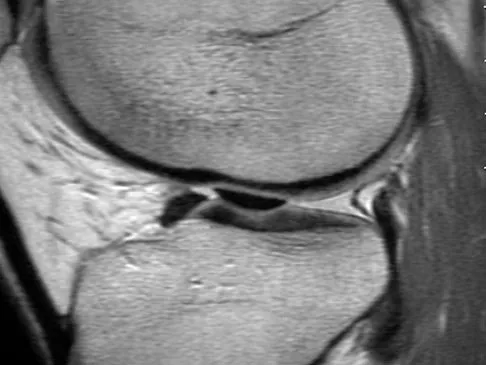

A 16-year-old boy sustains a twisting injury to the left knee while wrestling. MRI scans are shown in Figures 22a through 22c. What is the most likely diagnosis?

Explanation